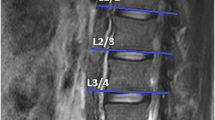

In this retrospective study, we randomly selected 60 MRIs (39 women and 21 men) of the lumbar region from a sample of a large cohort study, which was approved by the local ethics committee (EA1/058/21). MRI scans were conducted using a Siemens Avanto 1.5 T MRI system (Siemens AG, Erlangen, Germany) with T2-weighted turbo spin echo sequences for both axial and sagittal images. The axial T2 parameters used were a repetition time of 4.000, an echo time of 113, and a slice thickness of 3 mm. As the vast majority of degenerative changes can be detected in the lower spine, the levels L4–L5 and L5-S1 were evaluated.

All measurements were performed by two orthopedic residents, who were trained in the MRI muscle assessment. The MRI images were measured through the two different image processing programs (ImageJ and Amira). The two observers measured the MRIs in a random order for both investigators. The CSA of the multifidus muscle (MF) and erector spinae muscle (ES) was measured at mid-disk level L4/5 and L5/S1 (Fig. 1), the CSA was single measured before applying any thresholds. FCSA and FCSA/CSA were determined using two different segmentation thresholds for differentiating muscle fibers and fatty muscle infiltration.